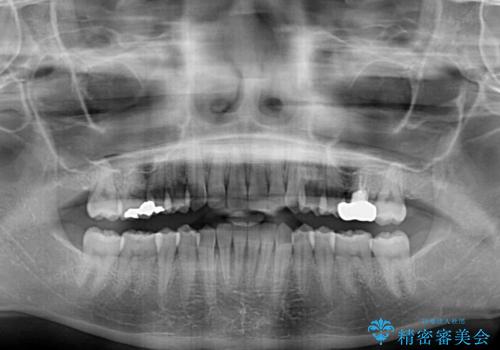

治療期間が世界的な感染症の流行時期と重なったため、海外と日本での往来が困難となり、治療継続が懸念されました。

それでも、しっかりとマウスピースを装着してくださったので、大きなトラブルもなく治療を終えることができました。